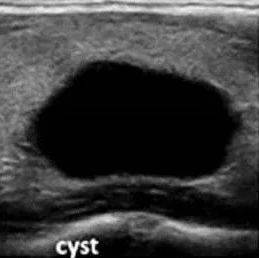

甲状腺结节“恶性风险”有多大?超声报告有解答

如何向病人解释结节的良恶性?